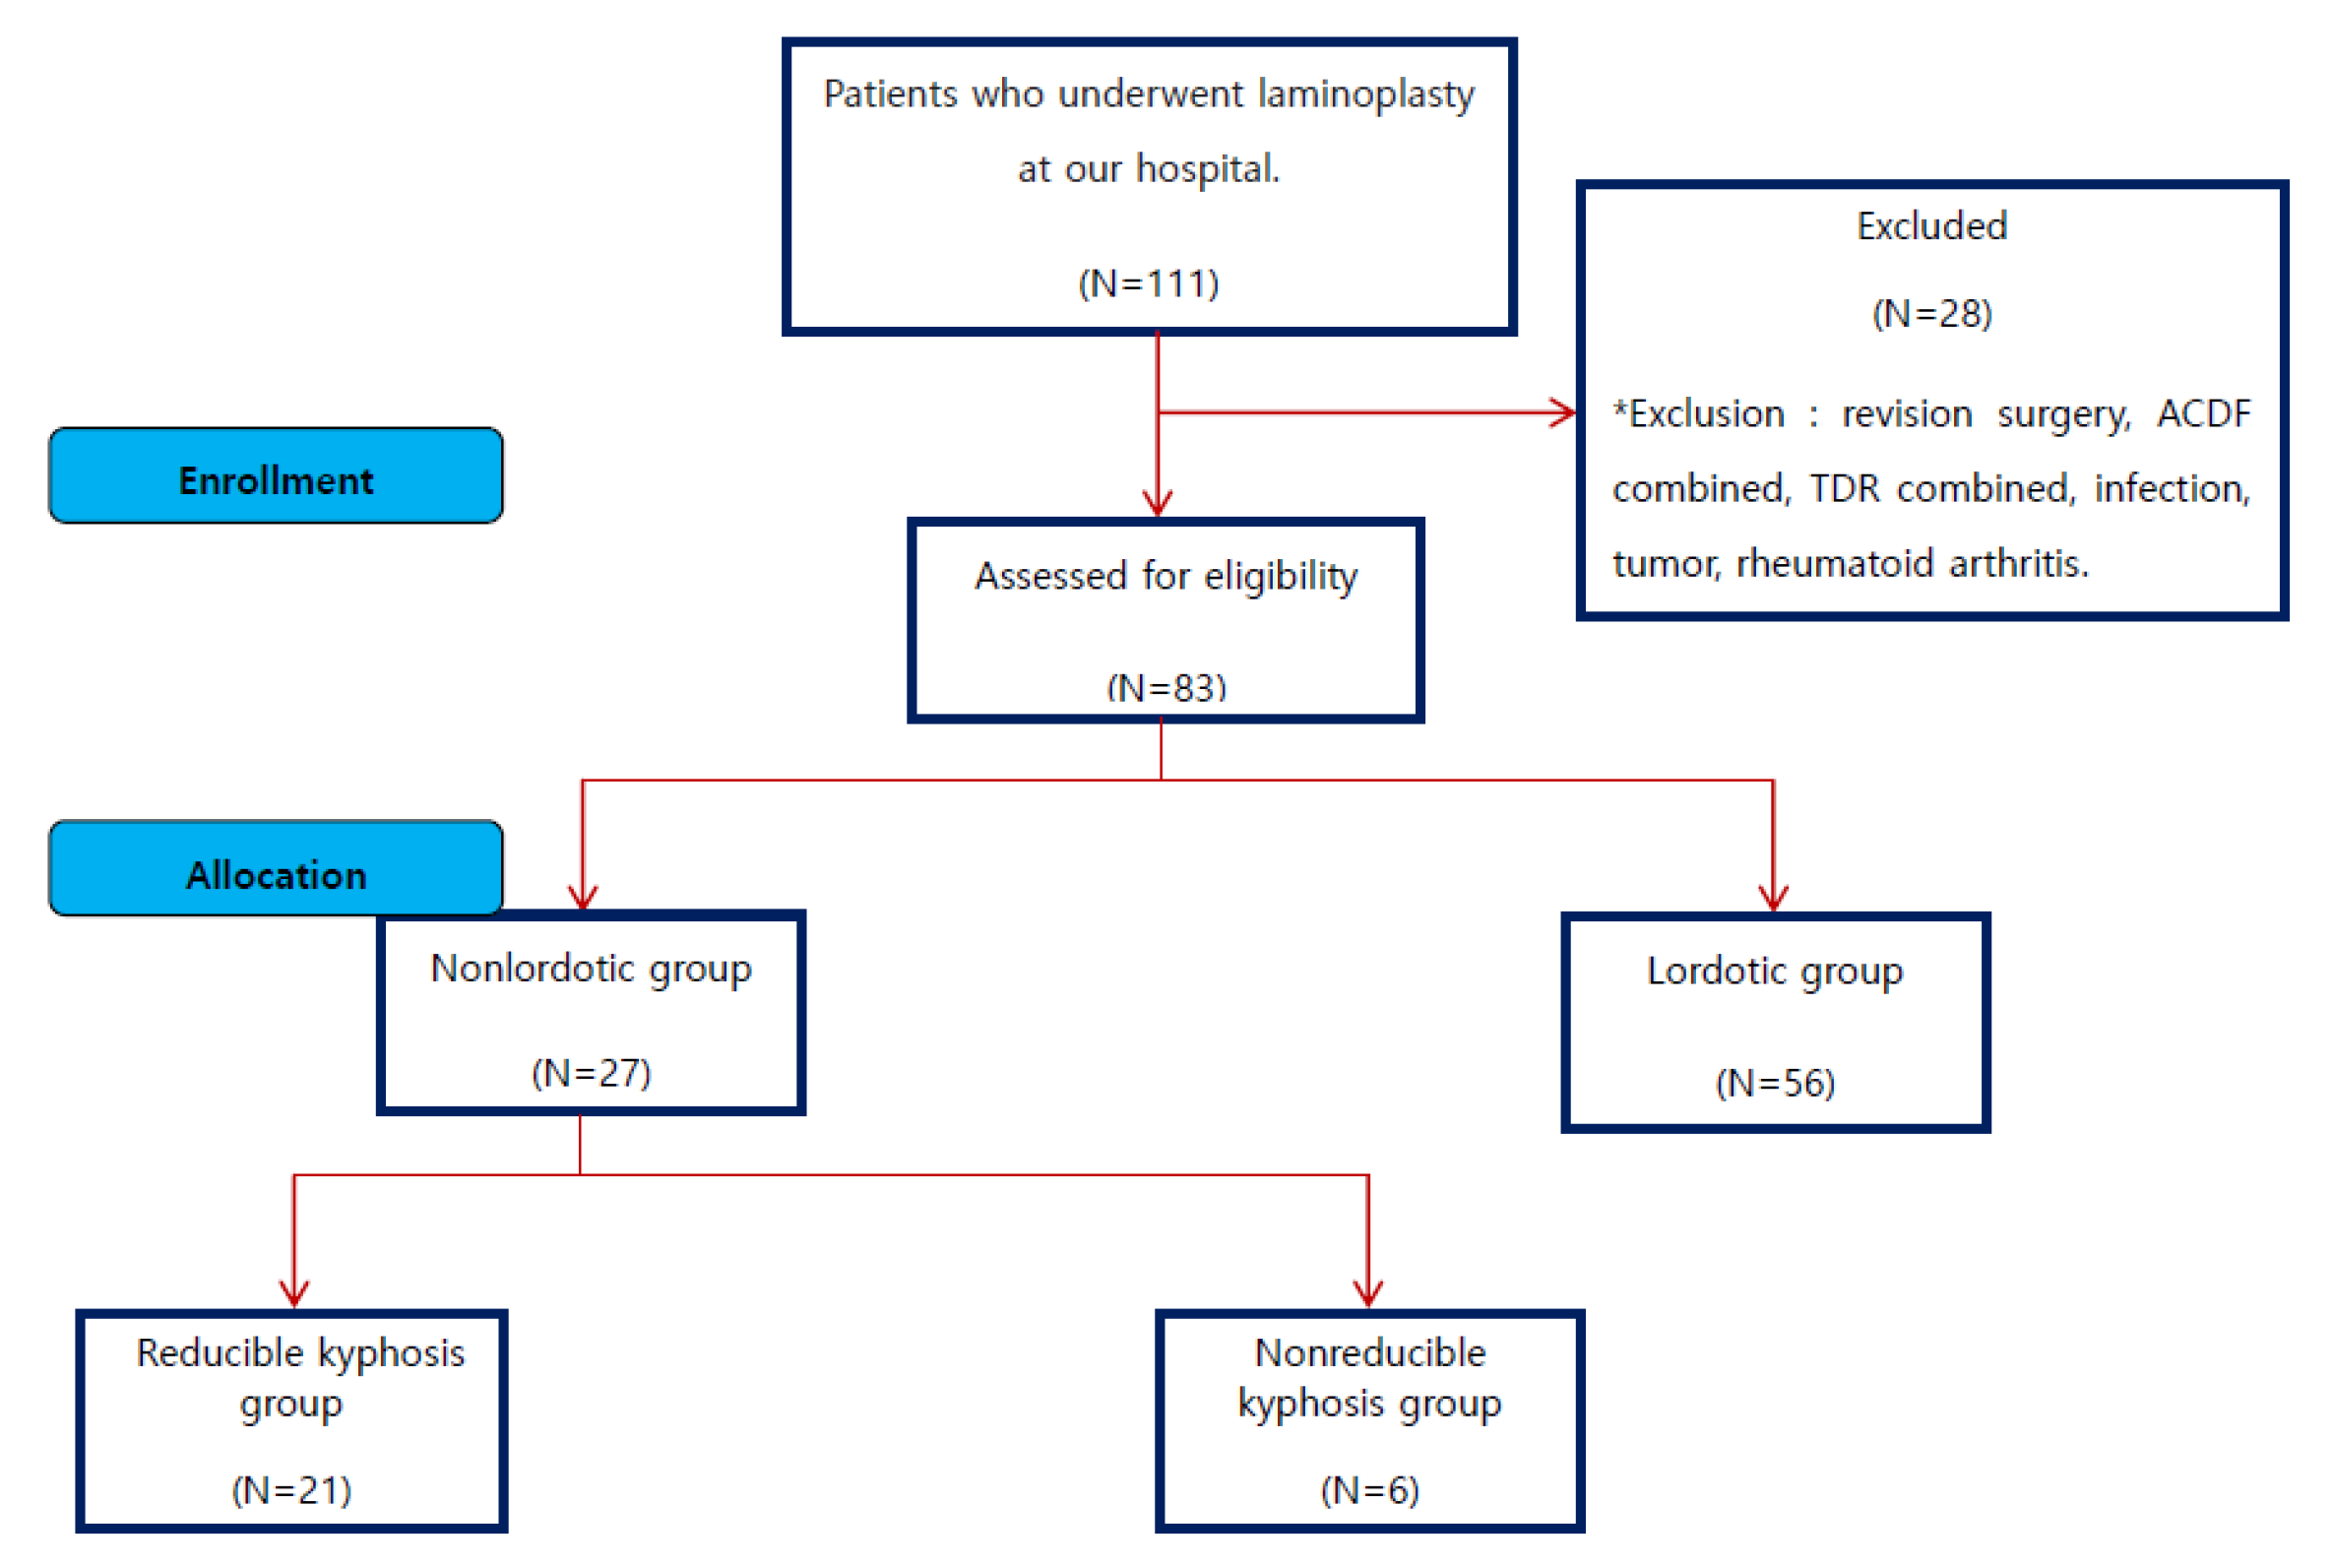

2. Materials and Methods

2.1. Research Subjects